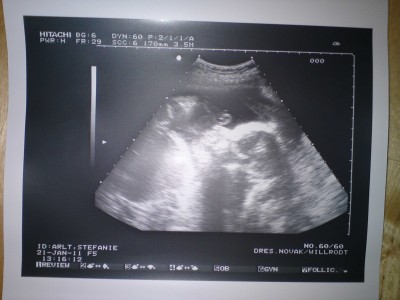

Das Baby war zum Glück nicht tot und es war wie immer ein tolles Erlebnis, so ein ausführlicher Ultraschall.

Auch ist alles bestens, die Nackentransparenz liegt bei 1,04 mm, also top.

Babylein misst 78,5 mm (SSL), mit Beinen ist er/sie also schon ca 12 cm groß (laut FA).

Sie hat heute auch eher zum Jungen tendiert, aber so richtig günstig lag das Baby heute nicht. Naja es bleibt echt spannend.

Nach dem Ultraschall sank mein Hintergrundrisiko für Trisomie 21 von 1.486 auf 1:2684, das Hintergrundrisiko für Trisomie 13/18 sank von 1:974 auf 1:5945, ich habe laut der FA ein Risiko wie eine 16-Jährige. Klingt alles gut.

Wir sind sehr happy und mein Mann war echt begeistert, was man da schon so alles sieht. Ich glaube, das war gut, dass er sein Kind auch mal in Aktion gesehen hat (Baby hat nämlich ausgesprochen wild geturnt

), so bekommt er eher eine Bindung und Vorstellung.

Anbei noch zwei Bildchen.